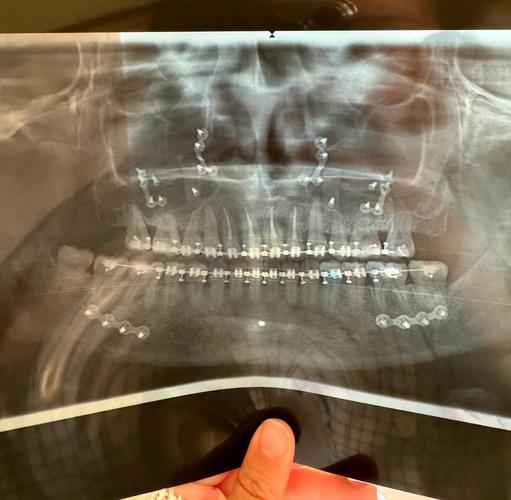

治疗前拍摄的基线视频能全面反映患者颌面问题,如通过侧面视频测量ANB角(上下齿槽座角)、SNA角(上齿槽座角)等骨性指标,结合动态咬合视频分析功能性错颌,为制定拔牙、扩弓、种植支抗等方案提供依据。

治疗中每3-6个月拍摄一次视频,可直观对比牙齿移动速度(如内收上颌前牙的进度)、面部轮廓变化(如下颌后缩患者的改善效果),及时发现异常(如咬合干扰、关节弹响),调整加力时机或矫治器附件。